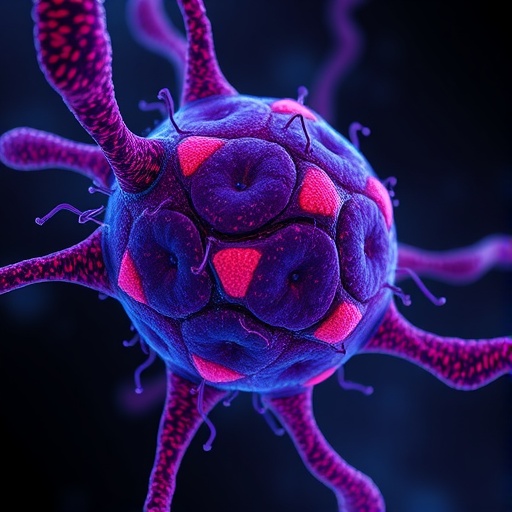

Üffing and colleagues zero in on one such alternative: autophagy. Autophagy, or “self-eating,” is a conserved lysosomal degradation pathway that recycles cellular components to maintain metabolic homeostasis. While autophagy is generally a survival mechanism under nutrient deprivation or stress, its role in cancer is paradoxical and context-dependent. In some settings, autophagy suppresses tumor initiation by limiting genome instability and chronic inflammation. Conversely, many established tumors, and especially those driven by RAS mutations, upregulate autophagy to meet elevated metabolic demands and survive in unfavorable microenvironments.

The authors meticulously dissect the complex interplay between RAS signaling and autophagic machinery. Oncogenic RAS fosters a rewiring of cellular metabolism that enhances nutrient scavenging, including reliance on autophagy-mediated degradation of intracellular constituents to sustain bioenergetic and biosynthetic processes. This metabolic rewiring enables cancer cells to thrive under hypoxic or nutrient-poor conditions, such as those imposed by a rapidly expanding tumor mass. Therefore, the study advances a compelling hypothesis that inhibiting autophagy could effectively ‘starve’ RAS-mutant tumors by cutting off a vital alternative supply line.

From a mechanistic standpoint, the study explores key nodes in the autophagy pathway that intersect with RAS-driven oncogenic signaling. For instance, downstream effectors of RAS, including mTOR and ERK, regulate autophagy initiation and flux, creating a finely tuned balance between growth promotion and catabolic recycling. Furthermore, RAS influences the expression of autophagy-related genes (ATGs), thereby enhancing the assembly and function of autophagosomes and lysosomes. Disruption of these pathways through genetic knockdown or pharmacological inhibition in experimental models led to marked reductions in tumor cell viability, underscoring the vulnerability imposed by autophagy dependence.